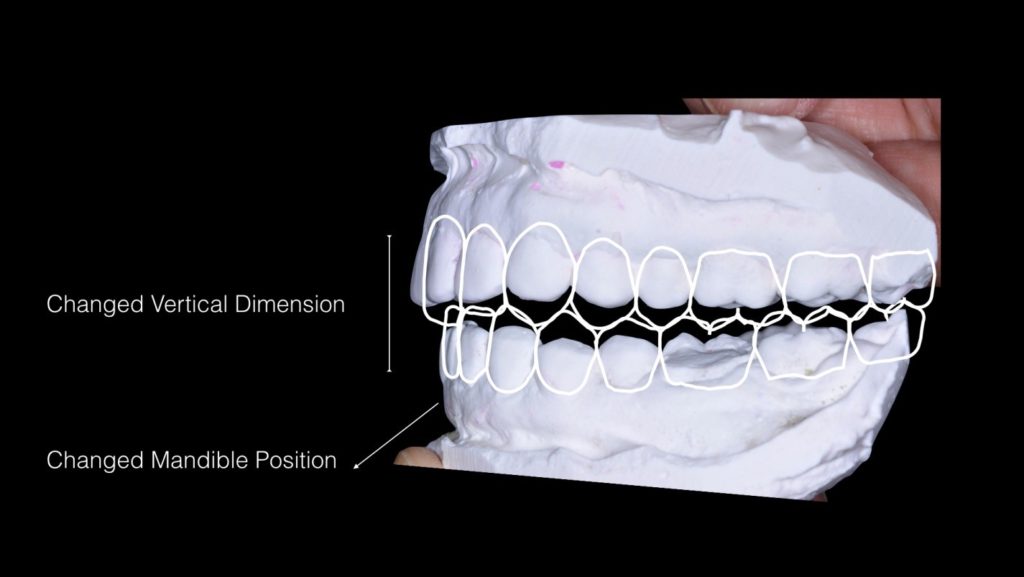

在全口重建的治療中,其精隨在於如何建立新的牙齒外型、新的咬合關係和新的咬合高度。因為咬合高度的喪失是經年累月所造成的,所以在全口重建的過程中,病人的適應性和耐心是絕對需要的。

另外沒有後牙穩定咬合關係的患者和深咬的患者,如此就必須將全口的牙齒進行重建,所以這樣一個全新的改變也必定是一個很大的工程。唯有病人和牙醫師的互相配合,全口重建才能順利的完成。

而且在許多的顳顎關節偏移治療的案例中,常會需要全口重建來配合作穩定咬合的治療。